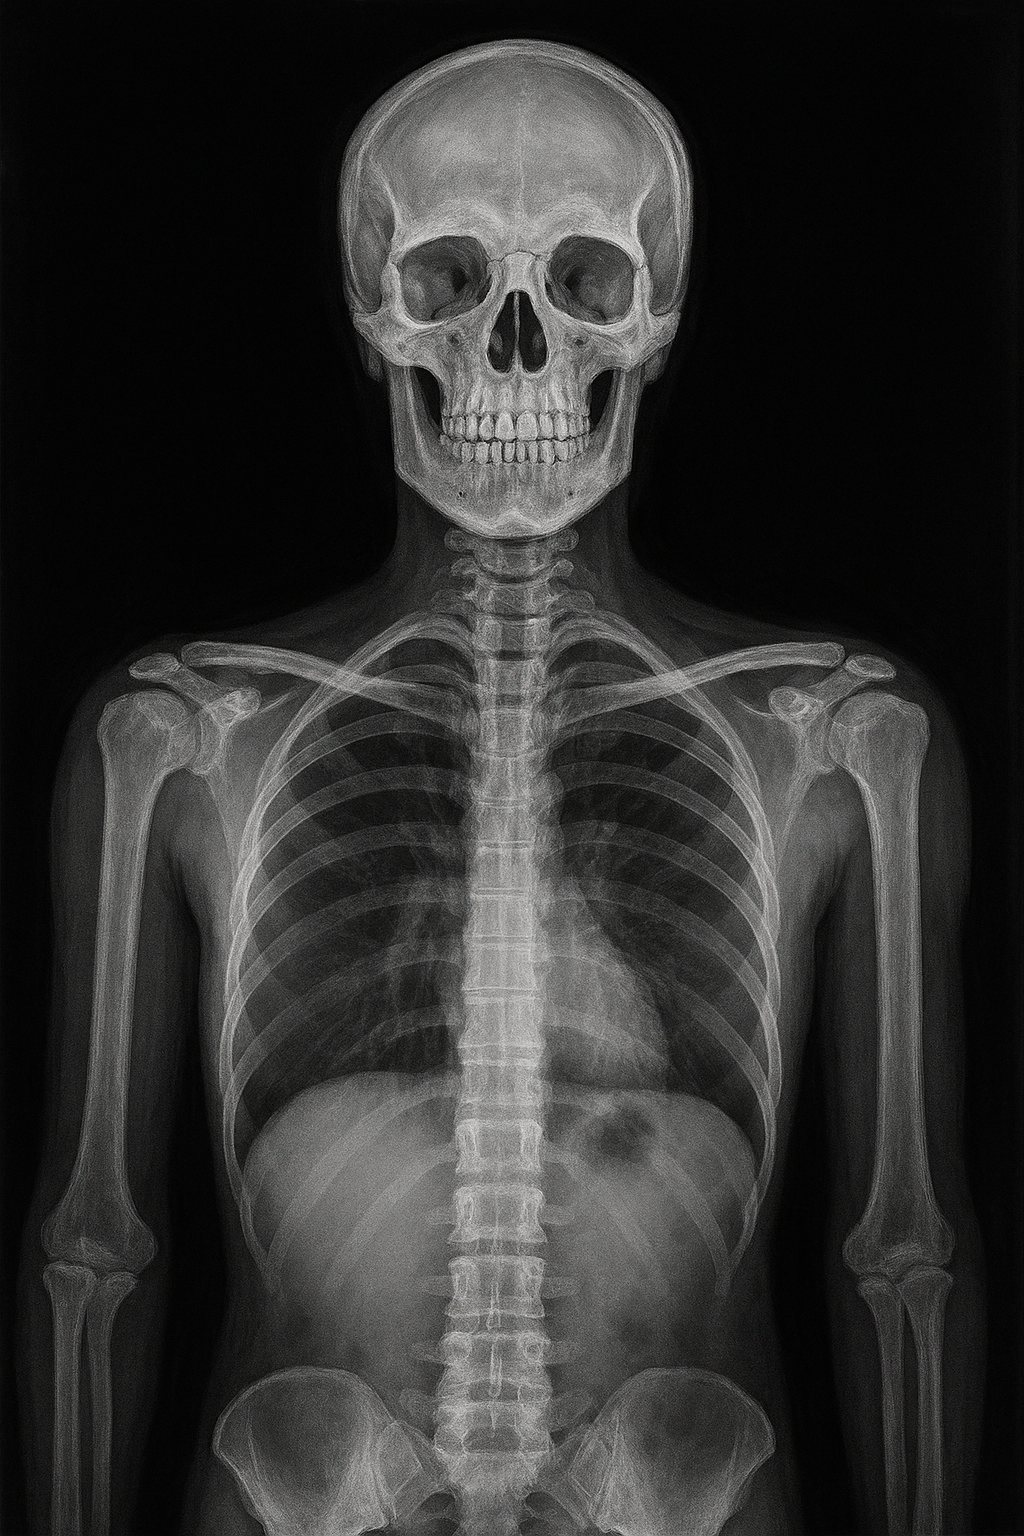

X-ray는 진공관 속에서 전자를 빠르게 가속시켜 금속에 충돌시키면서 발생하는 방사선입니다. 이 방사선이 인체에 투과되어, 조직 밀도 차이에 따라 필름이나 디지털 센서에 명암의 이미지를 만들어내죠.

- 뼈나 금속: 밀도가 높아 X-ray를 거의 통과하지 못하므로 하얗게 보임

- 근육, 장기, 지방: 통과가 가능하여 회색으로 보임

- 공기: 거의 투과되어 검게 보임